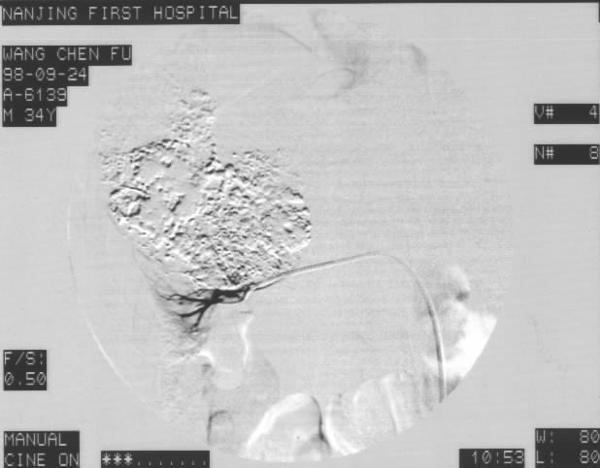

3. 治疗选择:根治性手术切除是肾癌的首选治疗方法,其他有介入治疗、激素疗法、化疗和免疫治疗等。介入治疗肾癌用于1.术前栓塞:手术前将肾动脉栓塞的优点主要在于减少术中出血,减少肿瘤经静脉转移的可能。肾动脉栓塞后24~72小时,被栓塞肿瘤和肾脏发生水肿,肾脏的界面显示得清楚, 有利于肿瘤的剥离和彻底切除。 2.单纯性介入治疗是对晚期肾癌无手术指征或不愿手术治疗病人的姑息治疗。目的是使肿瘤梗塞,可控制或缓解肿瘤所产生的严重症状,并使肿瘤缩小,稳定和改善全身状况,延缓肿瘤生长速度。

通常采用股动脉穿刺作腹主动脉造影或选择性肾动脉造影,在观察血管造影表现后,对肿瘤相关血管作选择性与超选择性灌注化疗药物和栓塞。栓塞可分为永久性或暂时性、完全性或不完全性。常用栓塞剂包括:无水酒精、明胶海绵、中药白芨粉、钢圈及碘油+抗癌药等。